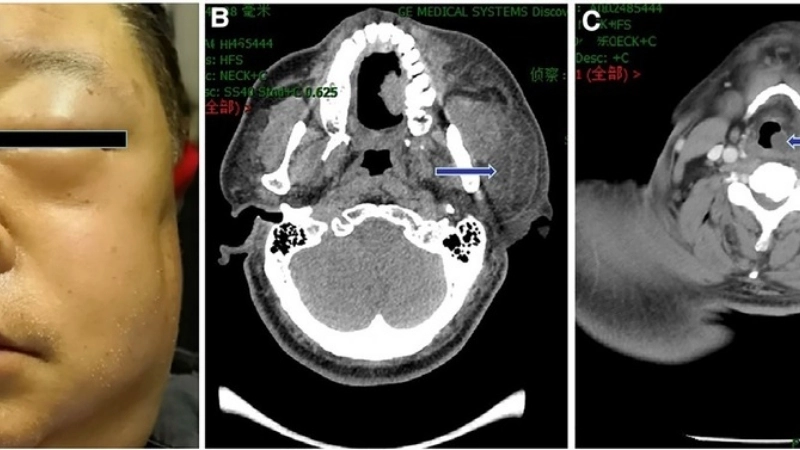

Hình ảnh triệu chứng bệnh quai bị sưng tuyến mang tai

• Triệu chứng bệnh quai bị điển hình nhất là sưng và đau một hoặc cả hai tuyến nước bọt mang tai, khiến một bên hoặc cả hai bên má phình to ra.

Vùng sưng đau do bệnh quai bị ở nam giới

Hình ảnh biến chứng bệnh quai bị viêm tinh hoàn